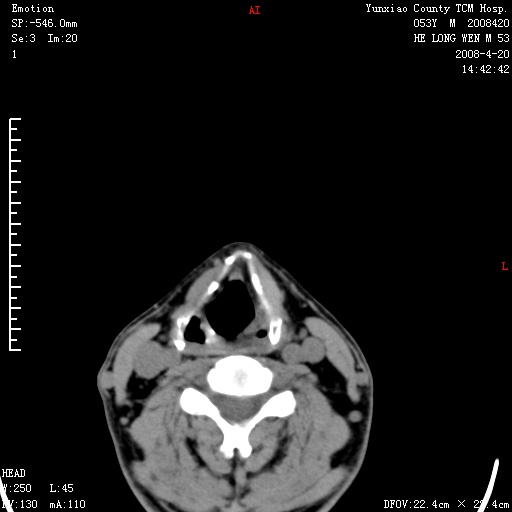

双侧扁桃体肿大:考虑化脓性扁桃体炎。

双侧扁桃体肿大 ,考虑扁桃体炎。

双侧扁桃体肿大,建议结合临床!

能强化就强化,不能强化就喉镜检查。如怀疑扁桃体肿大,应再往上扫

应该有症状,体检此部位不是常规体检项目,支持双侧扁桃体肿大 ,考虑扁桃体炎,但还是强化一下吧。

显示部分为舌扁桃体,腭扁桃体未见显示。会厌显示欠规则,建议喉镜。

病史太简单,体检?扁桃体是有增大,不会就这么简单吧?